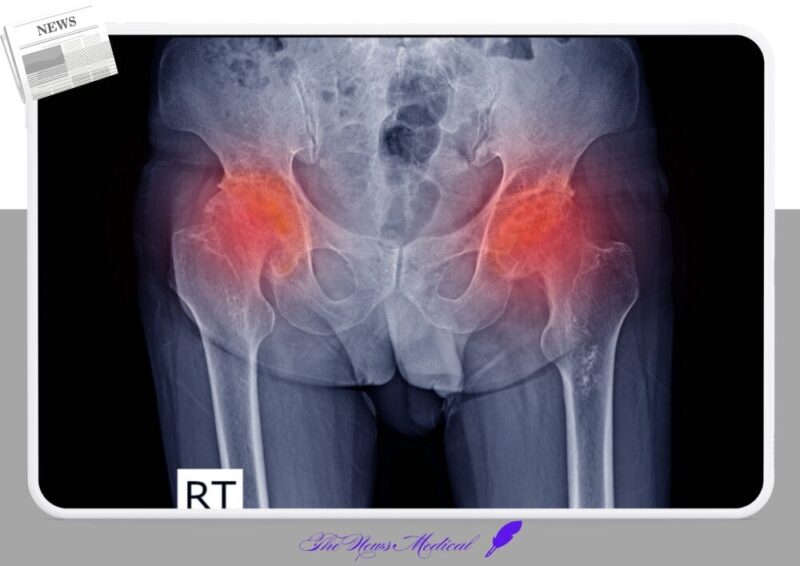

고관절은 우리 몸에서 상체와 하체를 연결하며 체중을 지탱하는 중요한 관절 중 하나다. 이 중 대퇴골두는 골반과 맞닿아 움직임을 조절하는데, 이 부위에 혈액 공급이 차단되면 뼈 조직이 서서히 괴사하는 대퇴골두무혈성괴사가 발생할 수 있다.

고관절 괴사를 조기에 발견하기 위해서는 X-ray, MRI, CT 검사를 통해 괴사의 진행 정도와 골절 여부를 확인해야 한다.